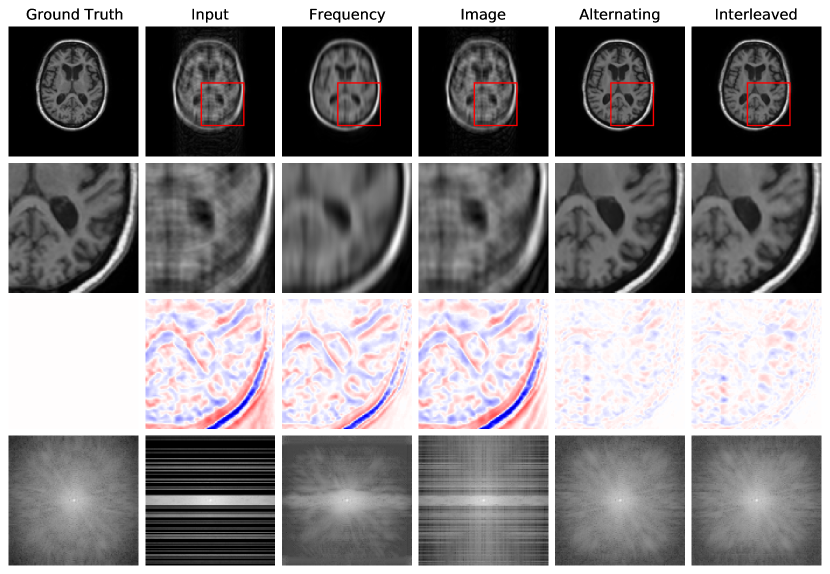

Fig. 4 reports reconstruction quality statistics for all four types of simulations described in Section 4.1.1: motion, noise, undersampling, and motion combined with undersampling. The Interleaved and Alternating architectures outperform the baseline architectures for nearly every task and subject. Across all tasks and nearly all subjects, the Interleaved and Alternating architectures are quite similar in numerical performance. Sample image reconstructions for the motion, motion with undersampling and denoising tasks are shown in Figs. 5-7. Qualitatively, for each task, the Frequency network provides a blurry version of the ground truth image. The Image network provides a reconstruction which effectively removes ‘background’ effects but has limited success in correcting these artifacts within the image. In contrast, the Interleaved and Alternating networks provide sharper, high-quality reconstructions across all tasks. Further, the frequency space reconstructions provided by those networks appear the most faithful to the ground truth frequency data.